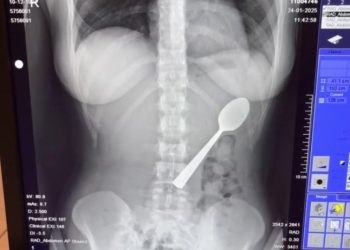

Read moreA 17cm-long spoon was found inside the body of a woman following an unexpected incident. The woman, identified as Reymy...